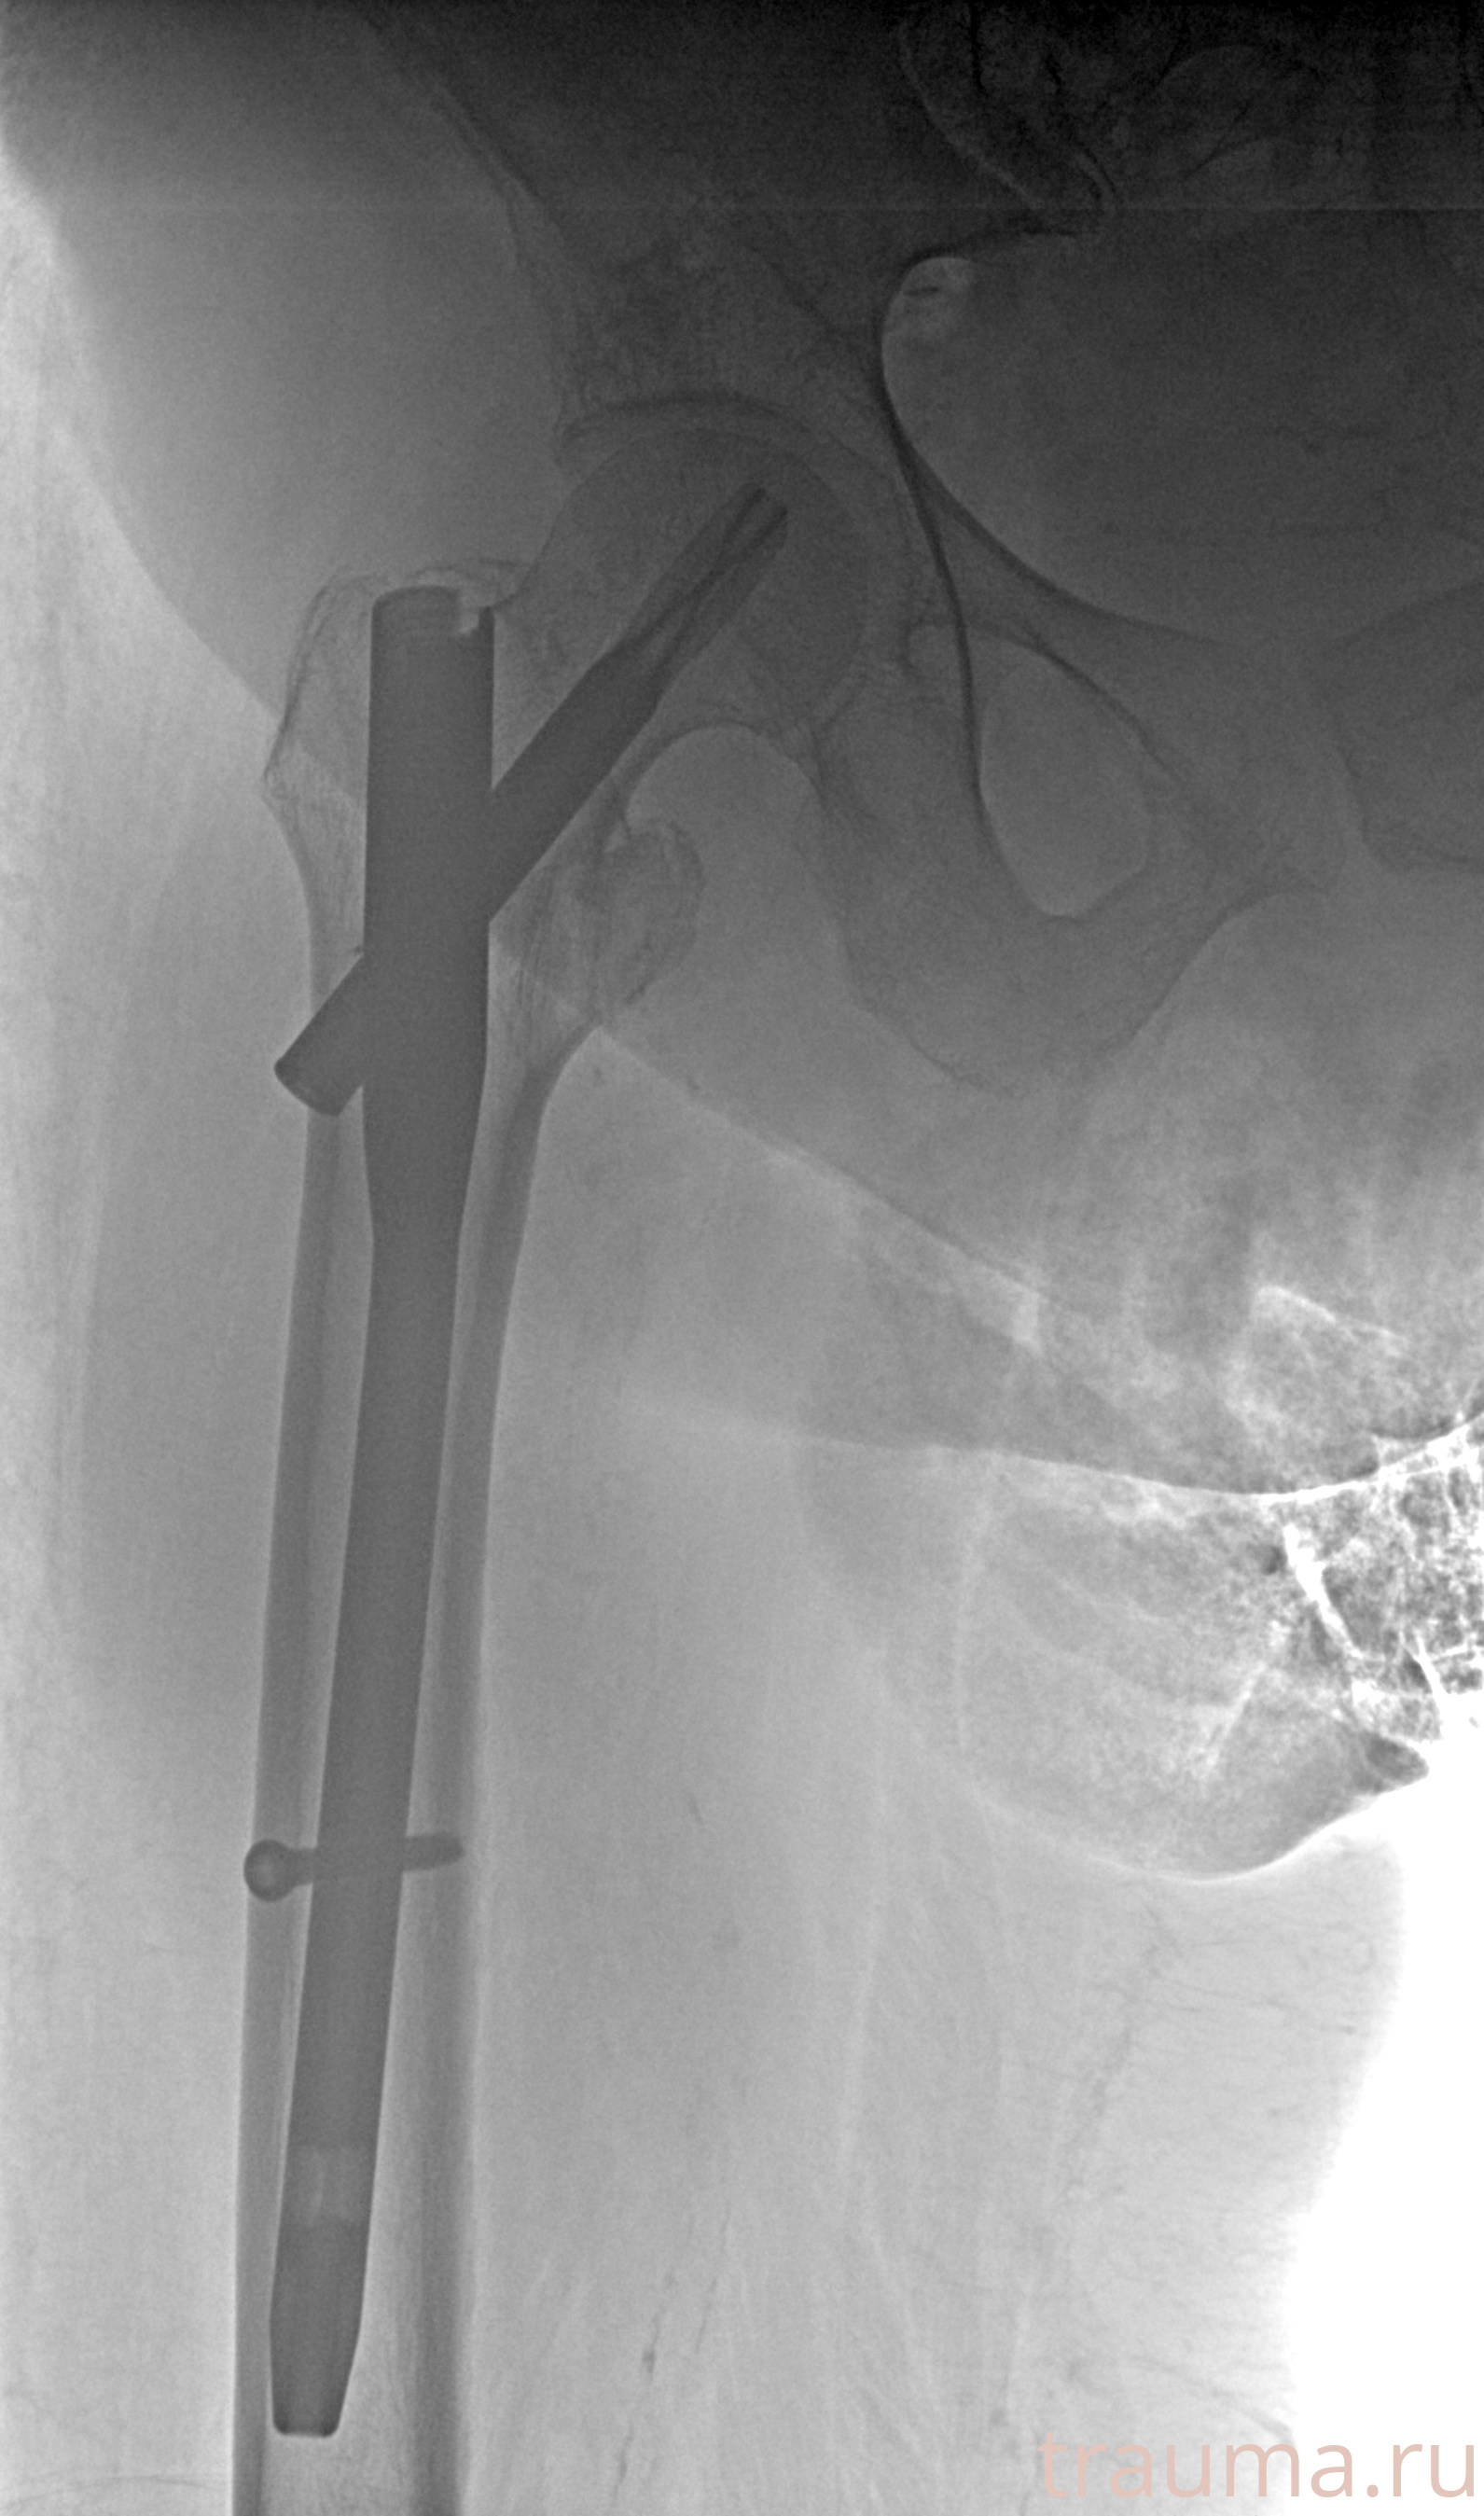

Рентгенограммы